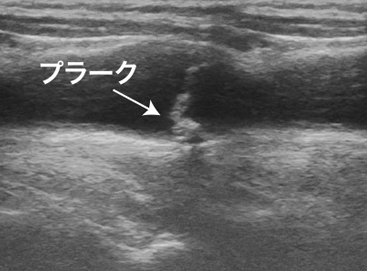

Arteriosclerosis

粥样动脉硬化

Plaque, arteriosclerosis